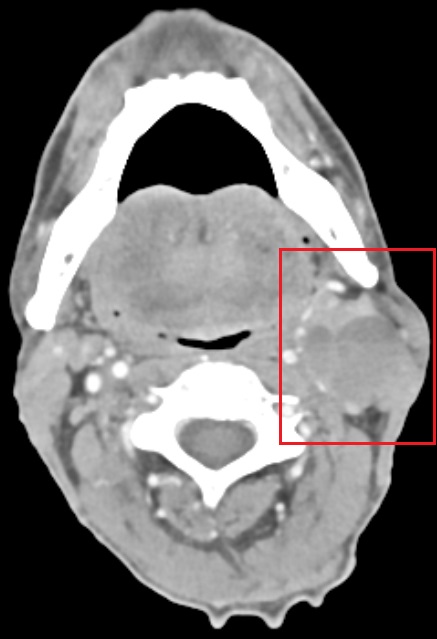

Ασθενής 63 ετών πρσήλθε με δυσκαταποσία και τραχηλική διόγκωση με επίταση της συμπτωματολογίας σε διάστημα τεσσάρων εβδομάδων. Η βιοψία της βλάβης στα πλαίσια πανενδοσκόπησης κατέδειξε την ύπαρξη πλακώδους καρκινώματος στο αριστερό ημιμόριο της βάσης της γλώσσας (Εικ.1). Η αξονική τομογραφία κατέδειξε την ύπαρξη συμπλέγματος λεμφαδενικών μεταστάσεων αριστερά με κυστική εκφύλιση (Εικ. 2). Μετά από λεπτομερή ενημέρωση του ασθενούς πραγματοποιήθηκε εκτομή του όγκου με τη βοήθεια μικροσκοπίου και διαστοματικής προσπέλασης με Laser CO2 καθώς και αμφοτερόπλευρος λεμφαδενικός καθαρισμός. Η ιστολογική εξέταση του όγκου κατέδειξε την ύπαρξη ενός Τ1 Ν2b G3 R0 p16 (-) καρκινώματος εκ πλακώδους επιθηλίου στη βάση της γλώσσας με βάθος διήθησης 9 mm κι ελάχιστη απόσταση 7mm από τα όρια εκτομής. Ο ασθενής έλαβε εξιτήριο την 3η ημέρα σε άριστη κατάσταση και σιτίζεται από το στόμα χωρίς πρόβλημα από την 7η μετεγχειρητική ημέρα.